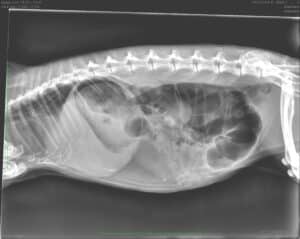

Radiographie 1 semaine avant l'accouchement, permet de compter le nombre de chiots, on compte les têtes ou les colonnes, dans ce cas 3 chiots